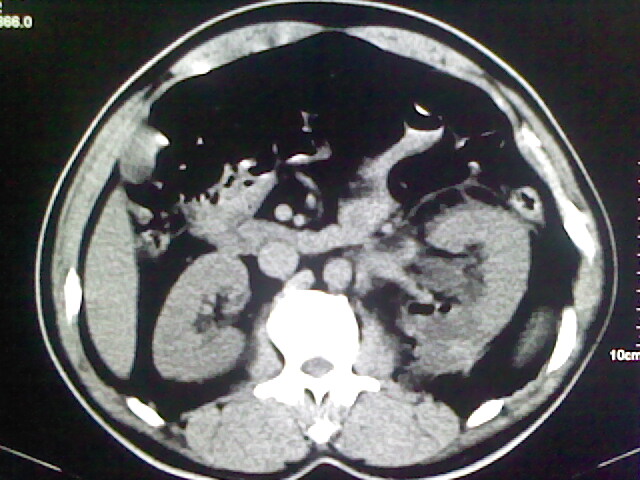

以下是引用zsl6918在2009-2-7 7:29:00的发言:[br]请提供介入的方式方法,肾及输尿管改变考虑与介入损伤有关,漏了,尿液外渗。

以下是引用余辉在2009-2-7 8:27:00的发言:[br]可能是硬化剂烧穿囊壁进入肾盂输尿管了,尿漏。不除外介入或碎石术后合并感染[br]患者术后怀疑结石,接着就碎石了?就怀疑没有确诊吗?碎石用的什么方法?气压弹道还是体外超声?如果这样的话责任人都难找

以下是引用随光逐影在2009-2-7 8:46:00的发言:[br]支持3楼意见。[br]另:不排除左肾及肾周感染可能。